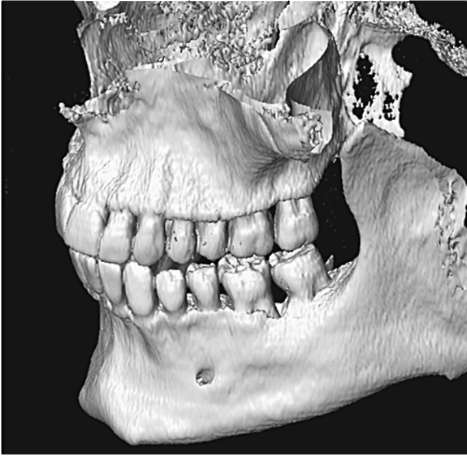

Исторически термин «биотип пародонта» введен С. Ochsenbein в 1969 г. На основании таких критериев, как высота и ширина коронок зубов, толщина альвеолярной кости и десны, а также величина зоны прикрепленной десны, им предложено выделять два биотипа пародонта: тонкий и толстый. Для тонкого биотипа характерны высокие и узкие коронки зубов, малая зона прикрепленной десны (рис. 4-7, см. цв. вклейку), множественные дигисценции (щелевидные дефекты альвеолярной кости с обнажением корня) и фенестрации корней (дефекты в виде окна). Толстому биотипу, как правило, свойственны короткие и широкие коронки зубов, большая зона прикрепленной десны (рис. 4-8, см. цв. вклейку), маргинальный костный контур массивный, фиброзный слой десны более выражен. Тонкий биотип пародонта встречается у 15% населения, толстый - у 85% соответственно. По данным М.Д. Петровой, средняя распространенность дигисценции корней (тонкого биотипа) составляет 20%.

В зависимости от биотипа пародонт по-разному реагирует на воспалительное повреждение, оперативное вмешательство и ортодонтическое лечение. Толщина вестибулярной костной пластинки определяет клиническое течение пародонтита. Воспалительная деструкция костной ткани - длительный процесс, развивающийся годами. Накопление таких провоспалительных факторов, как ИЛ-1 и фактор некроза опухоли-α (ФНО-α), способствует образованию остеокластов и усилению резорбции костной ткани. Естественно, скорость этой резорбции, приводящей к клиническим признакам пародонтита, напрямую зависит от объема костной ткани челюсти. Воспаление в костной ткани при развитии пародонтита в условиях толстого биотипа сопровождается образованием локальных пародонтальных карманов (рис. 4-9), резорбция альвеолярной кости и потеря клинического прикрепления при тонком биотипе проявляется в виде рецессий десны (рис. 4-10). Таким образом, при тонком биотипе пародонта с дефицитом костной ткани течение пародонтита носит более агрессивный характер вследствие ускоренной альтерации тканей. Прогноз лечения хронического пародонтита в данном случае менее благоприятный.

Рис. 4-9. Толстый биотип